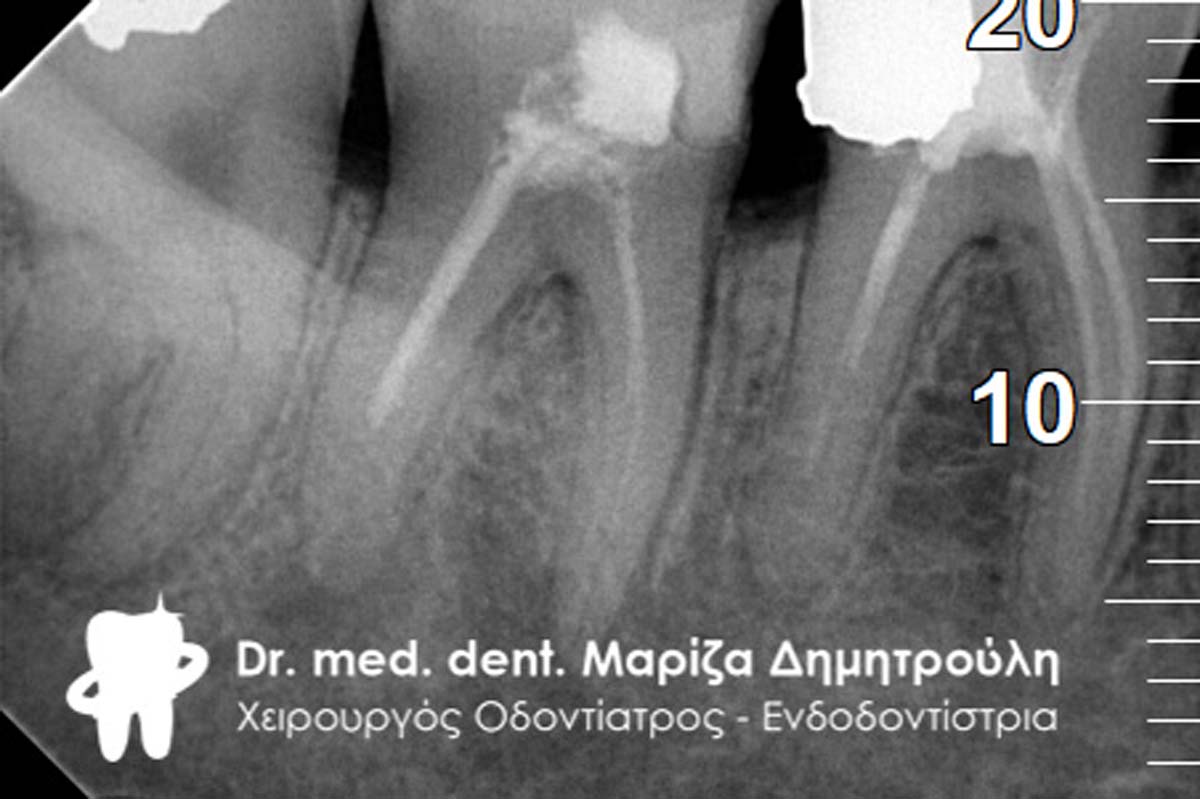

Η ασθενής επιθυμούσε να αντικαταστήσει 2 παλιά σφραγίσματα αμαλγάματος. Αποφασίστηκε η κατασκευή δύο ολοκεραμικών θηκών. Σύμφωνα με το γερμανικό πρωτόκολλο για τις απονευρώσεις δοντιών, πριν από μία προσθετική δουλειά θα πρέπει να ελέγχονται παλιές απονευρώσεις που υπάρχουν ήδη σε ένα δόντι. Σε περίπτωση που αυτές είναι αμφιλεγόμενες, τότε ενδείκνυται η επανάληψη απονεύρωσης, ώστε να μην προκύψουν στο μέλλον προβλήματα με το δόντι ενώ θα έχει κολληθεί η προσθετική δουλειά.

Στο συγκεκριμένο περιστατικό πραγματοποιήθηκε επανάληψη απονεύρωσης στο πρώτο δεξιό γομφίο. Στη διάρκεια της διαδικασίας εντοπίστηκε και τέταρτος ριζικός σωλήνας, ο οποίος δεν είχε βρεθεί στην πρώτη παλιά απονεύρωση. Η εγγύς ρίζα είχε ενασβεστιωθεί με τα χρόνια και δεν ήταν δυνατόν να επεξεργαστεί ο ριζικός σωλήνας σε όλο το μήκος του. Όμως όλες οι ρίζες παρασκευάστηκαν και καθαρίστηκαν πολύ καλά και στη συνέχεια εμφράχθηκαν ερμητικά.

ΠΡΙΝ

ΜΕΤΑ

ΜΕΤΑ- Προσπάθεια λήψης ακτινογραφίας του 4ου ριζικού σωλήνα του δοντιού